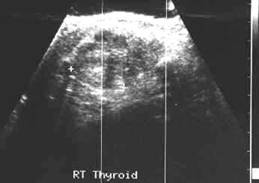

Ecostrutura omogena, normoecogena. Dimensiuni normale.

Se urmaresc rapoartele cu carotida, jugulara, muschii, traheea, esofagul.